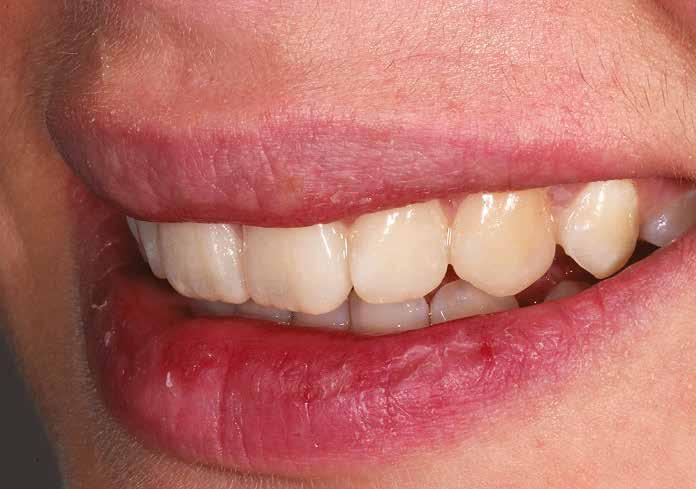

A cikkünkben bemutatásra kerülő eset ellátása során preparációt héjak készre vitele során a platinafólia technikát alkalmaztuk.

kívül vékonyak, és ezáltal a végleges rögzítésük előtt jelentős olyan minimál invazív kezelési eljárásnak számítanak, amely

elérni. A fent leírtak alapján bátran

preparációt nem igénylő héjak készítése mellett döntöttünk. A alkalmaztuk. Annak ellenére, hogy az elkészítésre kerülő héjak rendjelentős törésveszéllyel állunk szemben, összességében mégis amely segítségével kifogástalan esztétikai eredményeket lehet javasoljuk e módszer alkalmazását.

A fogászati kezelések során manapság már nem kizárólag az esztétikai megjelenés helyreállítására törekszünk. Sokszor a kedvezőtlen esztétikai megjelenés hátterében álló okok következményes módon a fogazat funkcionális működését is károsítják, így a kezelések során ezeknek a helyreállításával is foglalkoznunk kell. A különböző funkcionális és esztétikai diszkrepanciák kezelésére számtalan módszer létezik, ám ezen fogászati beavatkozások mindegyikében közös, hogy a kivitelezésük során nagyon szoros együttműködésre van szükség a kezelést végző fogorvos és a munkáját segítő fogtechnikus között. Az alábbi esetbemutatás során egy fiatal hölgypáciens fogazatának héjak alkalmazásával történő esztétikai és funkcionális rehabilitációját szeretnénk ismertetni.

Esetbemutatás

A 19 éves hölgypáciens azzal a kéréssel jelentkezett a rendelőnkbe, hogy szebb fogakat szeretne. Az első konzultáció alkalmával megkérdeztük, hogy mi zavarja leginkább a fogazatának jelenlegi megjelenésében, valamint azt is megbeszéltük vele, hogy milyen végeredmény elérése esetén lenne maradéktalanul elégedett. Ebben az esetben a kezelési célokat az alábbiakban határoztuk meg:

A páciens fogazata esztétikai megjelenésének és funkcionális működésének a lehető legtöbb, saját foganyag megtartása mellett történő helyreállítása (1. és 3. ábra). A lehető legideálisabb esztétikai végeredmény elérése érdekében néhány esetben a fogak alakjának módosítá -

sára is szükség van (2. és 4. ábra).